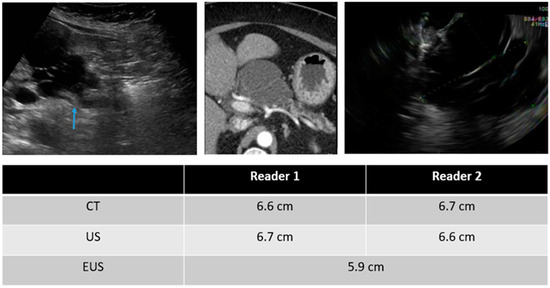

| Mean size of detected PCLs (cm) | ||

| TAUS | 2.40 ± 2.65 | 2.41 ± 2.56 |

| CT | 2.45 ± 2.43 | 2.48 ± 2.53 |

| EUS * | 2.73 ± 2.10 | |

| Intra-reader variability in measured size | Reader 1 vs. Reader 2 | |

| TAUS | −0.01 ± 0.39 | |

| TAUS vs. CT | TAUS vs. EUS | CT vs. EUS | |

| All PCLs (cm) | |||

| Reader 1 | −0.16 ± 0.53 * | 0.13 ± 1.14 | 0.15 ± 0.65 * |

| Reader 2 | −0.19 ± 0.55 * | 0.18 ± 0.81 | 0.22 ± 0.90 |

| Tail | |||

| Reader 1 | −0.37 ± 0.23 * | −0.75 ± 0.35 | −0.35 ± 0.64 |

| Reader 2 | −0.13 ± 0.38 * | −0.45 ± 0.07 | −0.35 ± 0.50 |